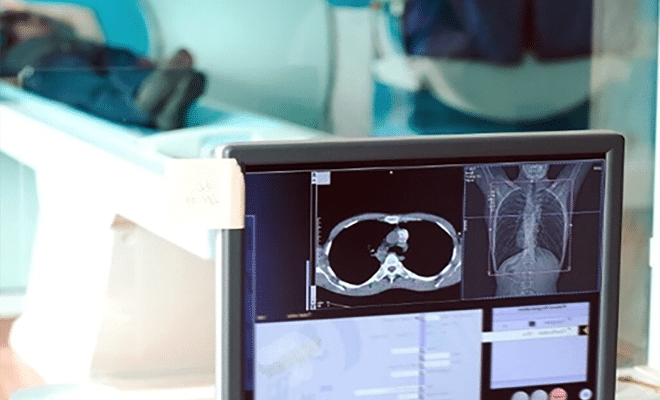

Diagnostic Imaging Tests

X-ray and CT scans are diagnostic imaging tests which examine the chest area to locate and stage abnormal-looking masses or growths that may be tumors.

Common imaging tests doctors use to start a diagnosis include:

- X-ray

- Magnetic resonance imaging (MRI)

- Computerized tomography (CT) scan

- Positron emission tomography (PET) scan